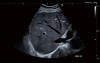

Canon Aplio i800 – kardiologiya, doğuş və ginekologiya (OB/GYN), muskuloskelet (MSK), damar və ümumi görüntüləmə daxil olmaqla geniş klinik sahələr üçün nəzərdə tutulmuş premium ultrasəs diaqnostika sistemidir. Canon-un i-seriya platforması əsasında hazırlanmış bu model yüksək diaqnostik dəqiqlik, sabit görüntü keyfiyyəti və müasir iş axınının optimallaşdırılması üçün qabaqcıl texnologiyalarla təchiz olunub.

Aplio i800 intensiv iş yükü olan tibbi müəssisələr üçün etibarlı, çoxfunksiyalı və performans yönümlü həll təqdim edir. İnnovativ görüntüləmə funksiyaları, ağıllı avtomatlaşdırma alətləri və ergonomik dizayn sayəsində həkimlərin işini asanlaşdırır, pasiyent müayinəsinin keyfiyyətini artırır. Geniş prob seçimi və güclü emal texnologiyası i800-ü hərtərəfli klinik istifadə üçün ideal edir.